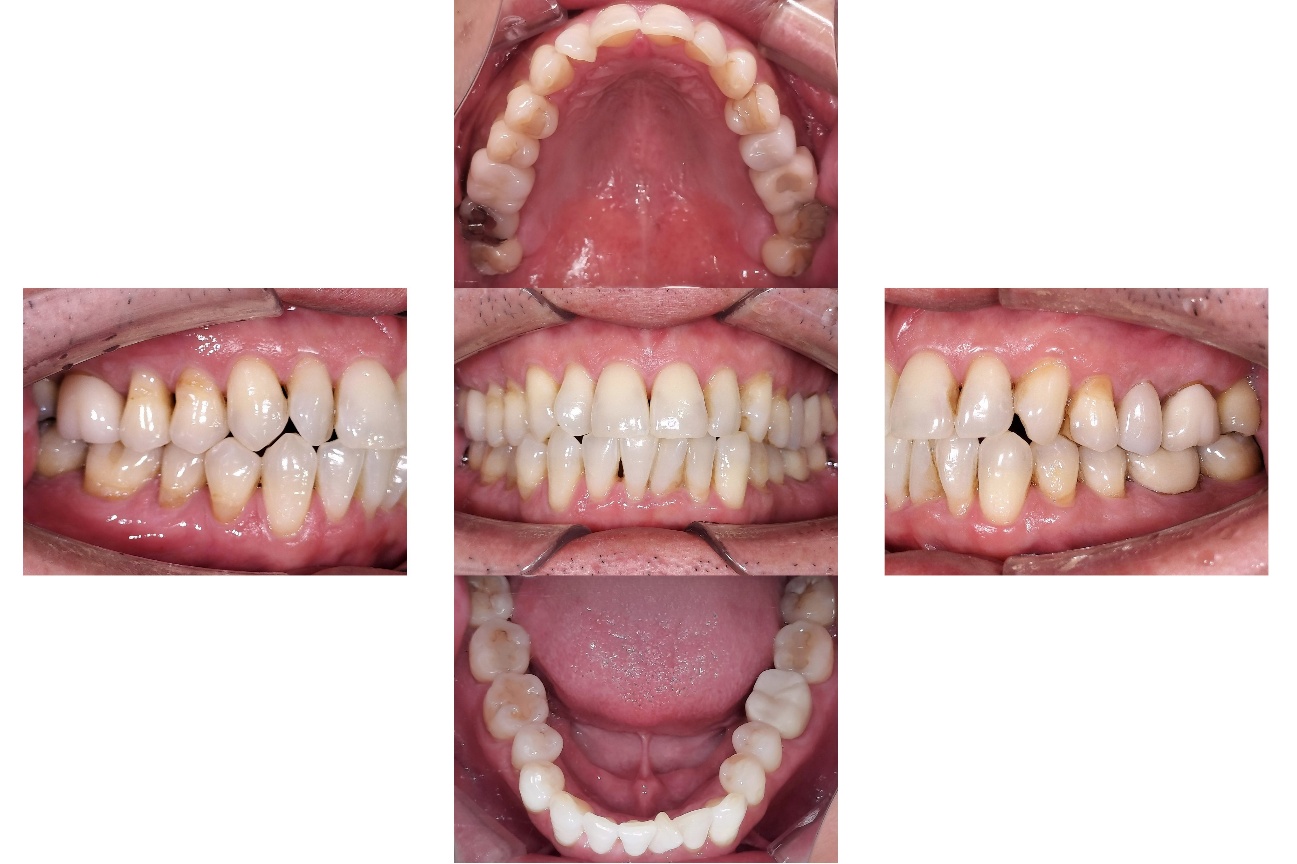

Before

After

【矯正治療】マウスピース型矯正装置(インビザライン)による全顎矯正

【補綴治療】詳細は表内の費用欄に掲載

【矯正治療】10か月

【補綴治療】約5か月

【矯正治療】12回

【補綴治療】14回

【矯正治療】¥957,000(税込)

【補綴治療】

【矯正治療】